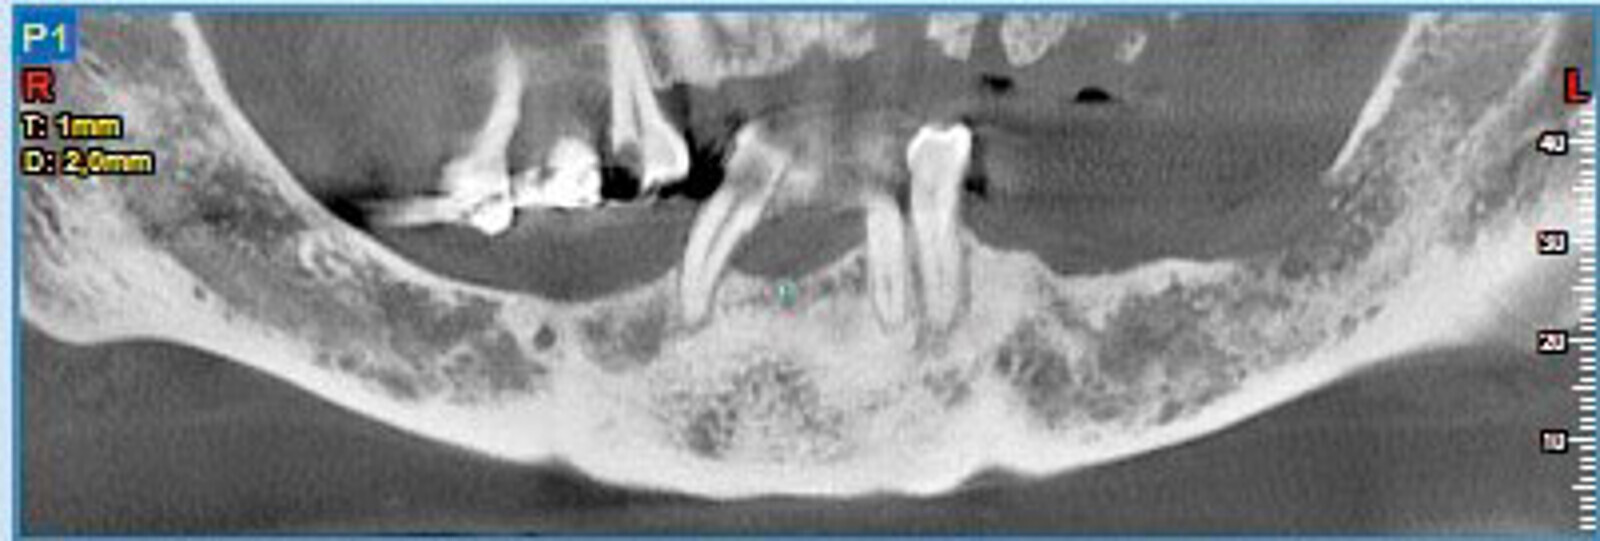

Protocollo SKY fast & fixed